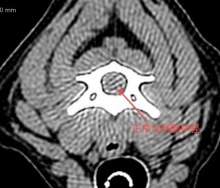

CTの検査をおこなうと、頸椎の第2ー3番の間に重度の椎間板の脱出があり、頚椎椎間板ヘルニアと診断しました。

次に、横の画像がリリーちゃんの圧迫を受けている頸椎のCT画像です。上の写真に比べると、下側から、大量の椎間板物質に圧迫されているのがよくわかりますよね。